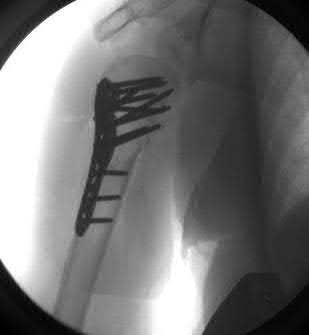

A 68-year-old osteoporotic female sustains a proximal humerus fracture. The AP radiograph is shown. According to the Hertel criteria, which of the following radiographic features is the most reliable predictor of humeral head ischemia?

Options:

- Anatomical neck fracture pattern

- Greater tuberosity displacement > 1 cm

- Metaphyseal head extension (calcar segment) less than 8 mm

- Varus angulation greater than 20 degrees

- Disruption of the medial periosteal hinge > 2 mm

Correct Answer: Metaphyseal head extension (calcar segment) less than 8 mm

Explanation:

Hertel et al. described radiographic criteria predictive of humeral head ischemia. The most reliable predictors include a metaphyseal head extension (calcar segment) of less than 8 mm, disruption of the medial hinge (>2 mm), and an anatomic neck fracture. Among the choices, the calcar segment length < 8 mm represents a highly predictive sign that the primary blood supply (the ascending branch of the anterior humeral circumflex artery and intraosseous vessels) has been severely compromised.